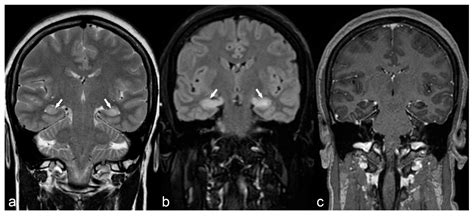

The human brain is a dynamic organ that undergoes various changes throughout a lifespan. Parenchymal volume loss, or cerebral atrophy, is essentially the loss of neurons and the connections between them. As the brain loses these cells, the physical space they occupied diminishes. This can manifest as an expansion of the sulci (the grooves on the surface of the brain) or the enlargement of the ventricles (the fluid-filled spaces inside the brain).

When a radiologist identifies volume loss, they usually assess the distribution of the atrophy. Generalized atrophy refers to widespread loss across the entire brain, while focal atrophy suggests that specific areas, such as the hippocampus or the frontal lobes, are being disproportionately affected. The following table provides a snapshot of how medical professionals categorize these findings:

The interpretation of a brain scan is rarely done in isolation. A radiologist or neurologist will compare the scan against the patient's history. For example, a 75-year-old patient with mild memory complaints and parenchymal volume loss may be viewed very differently than a 40-year-old with similar findings on an MRI. In younger patients, unexpected volume loss often triggers a deeper search for underlying causes, such as autoimmune disorders, chronic alcohol use, or nutritional deficiencies.

Technological advancements in "volumetric MRI analysis" now allow doctors to quantify brain volume more precisely than in the past. These automated programs can compare a patient's brain size to normative databases, providing a more objective measure of whether the observed loss is truly abnormal for the patient's specific age and biological sex.